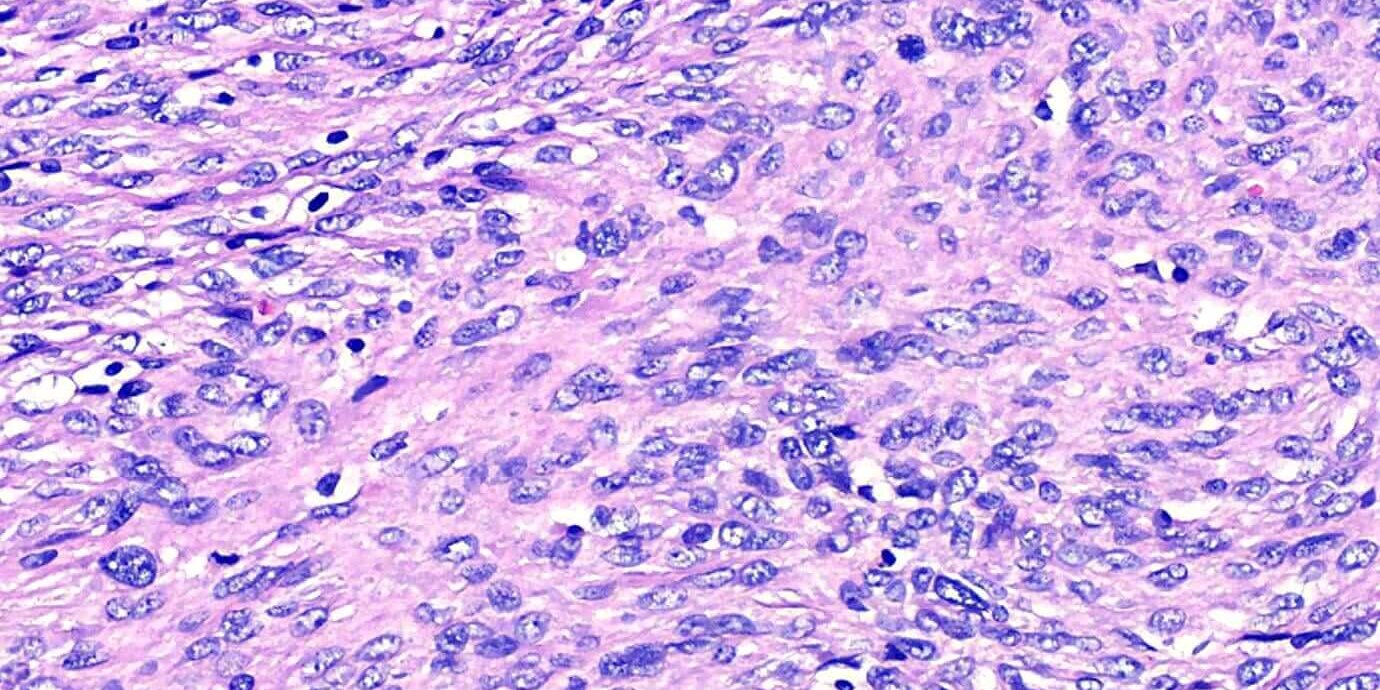

本病例是一個犬的皮膚腫瘤,臨床醫師在手術時一併採集了周圍的淋巴結。檢查結果發現,淋巴結嚴重被腫瘤侵犯,有大半的淋巴結組織消失。組織病理學發現這個結果,臨床就須要特別注意患病動物未來是否有內臟出現轉移的狀況,可以即早與飼主對治療計劃進行溝通。

透過這個病例,也提醒我們病理檢查的重要性,如果醫師沒有將淋巴結組織送檢,可能就無法發現腫瘤已經轉移了。手術切除的腫塊,不論經驗或細胞學檢查結果為何,所有外科檢體都應該進行病理學檢查,才能提供患病動物最準確的治療方向!